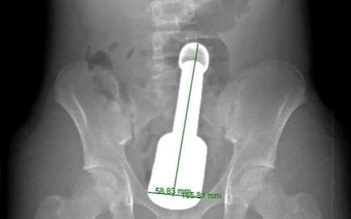

Chày kim loại kẹt trong trực tràng khiến thiếu niên 15 tuổi phải cấp cứu trong đêm